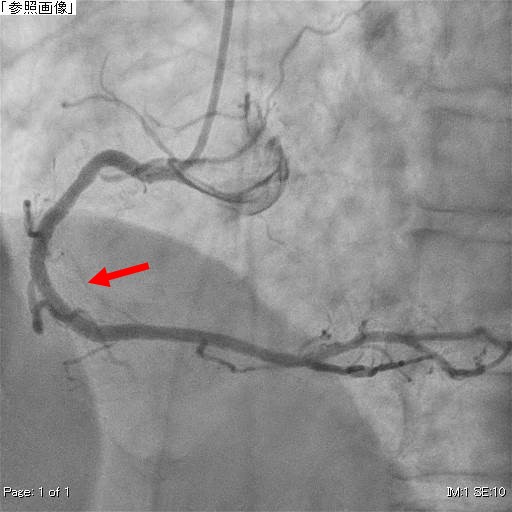

右冠動脈造影(PCI後)

同部位にバルーン、ステント治療を施工し改善された